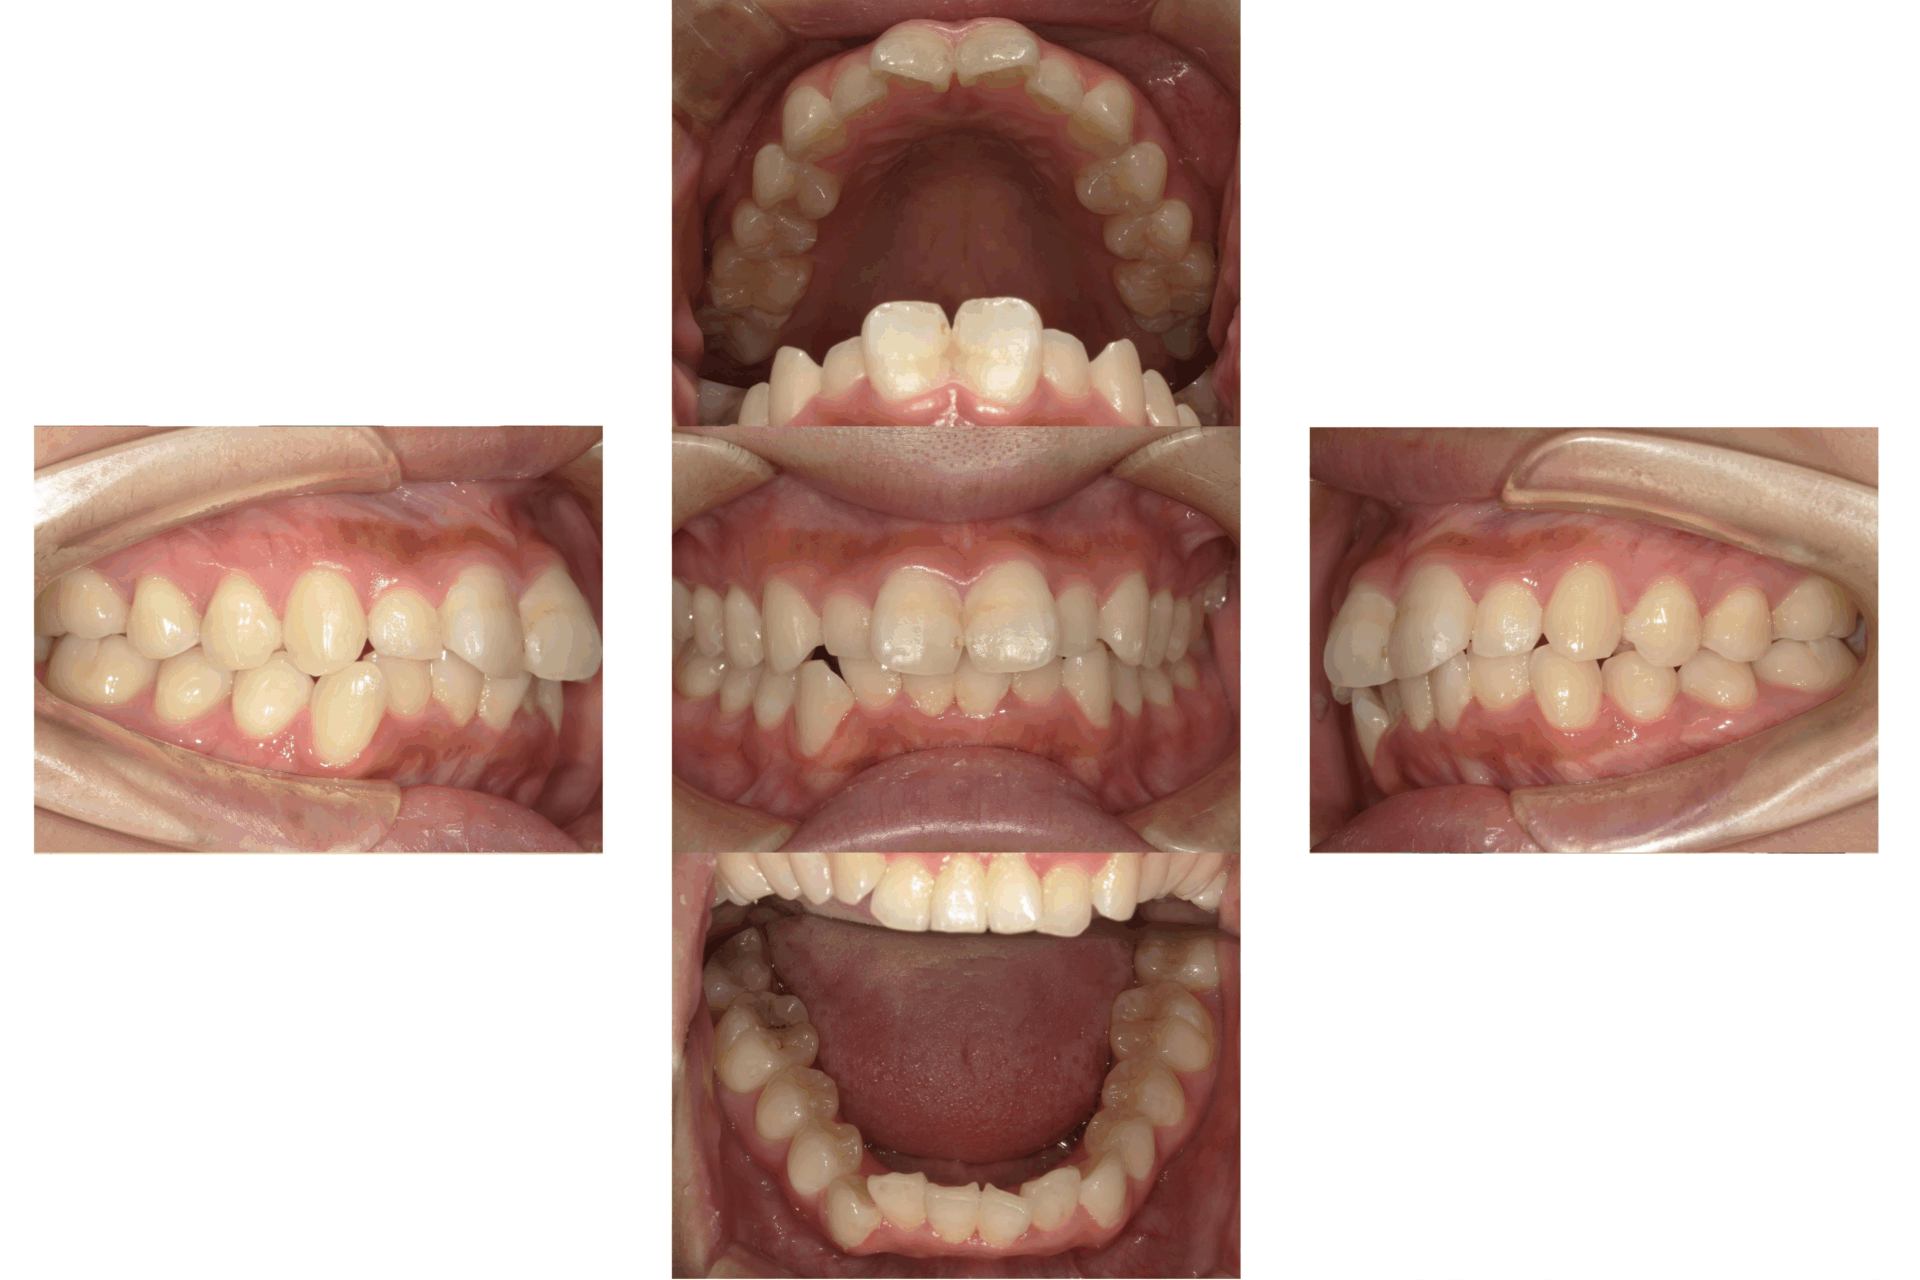

10代、女性、ワイヤー

| 施術内容 | 主訴:上下前歯でこぼこ。なるべく抜きたくない。 詳細:ワイヤー矯正での歯並び改善 詳細:ワイヤー矯正での歯並び改善 歯肉炎リスクあるため、今後は後戻りのチェックとともに歯肉炎管理もしていきます。 |

| 治療期間 | 12ヶ月(2/6現在 治療終了) |

| 費用 | ワイヤー矯正 60万円(税込660,000円) |